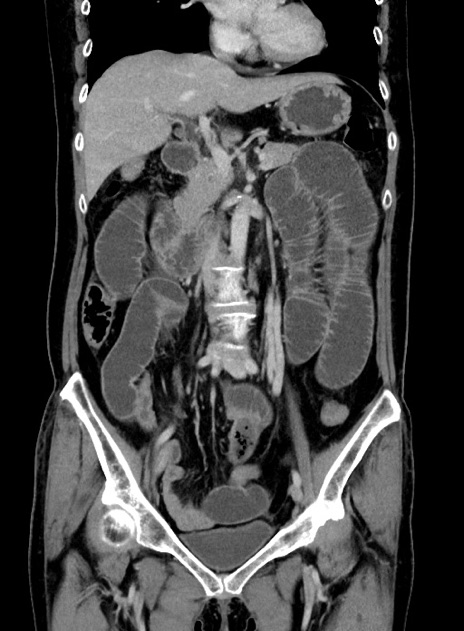

横断像

【症例】 60歳代女性

【主訴】むかつき、みぞおちの痛み

【現病歴】3日前よりむかつきがあり、食事がとれない。

【既往歴】糖尿病

【身体所見】発熱なし、心窩部圧痛軽度あるも、腹膜刺激症状なし。

【データ】WBC 7400、CRP 1.92